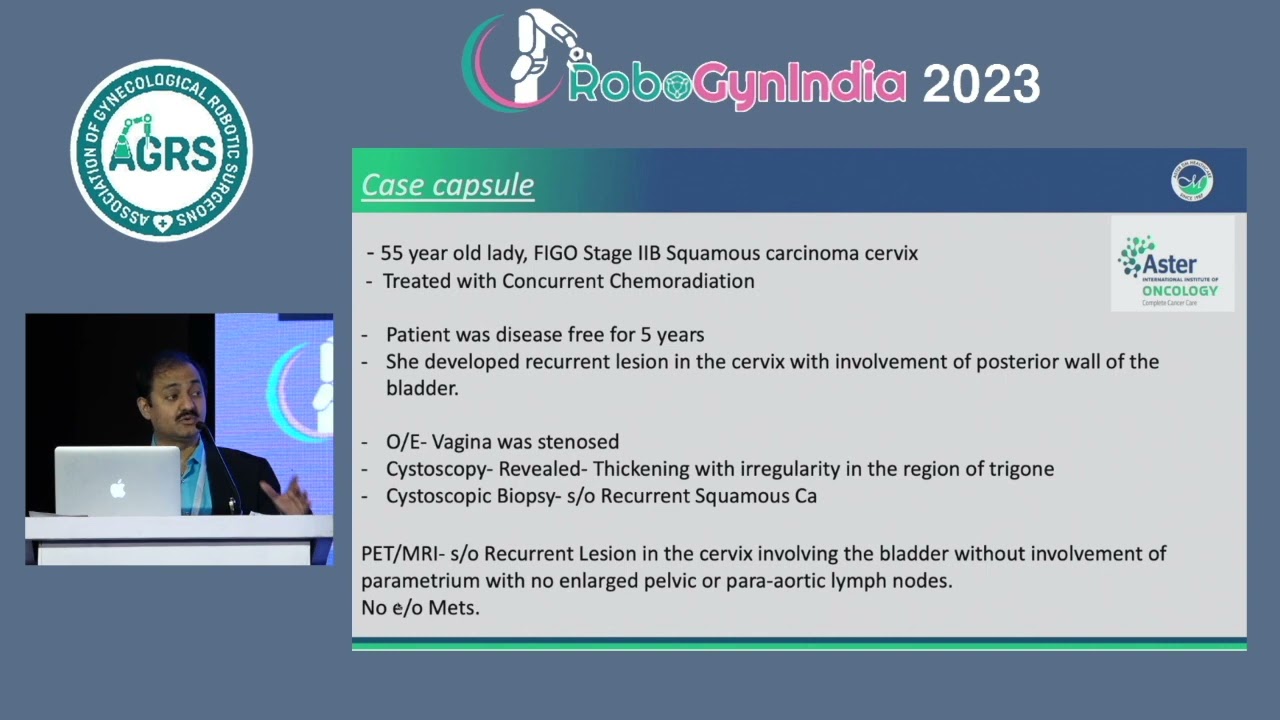

RoboGynIndia Robot Assisted Myomectomies-across the complexity spectrum

Gynecology, Masterclass, Robotics, Surgeon ';

RoboGyIndia ’23 Day 2 AGRS Vattikuti Scholars Session

Gynecology, Masterclass, Robotics, Surgeon ';

Day 2 RoboGynIndia Lectures by Masters

Gynecology, Masterclass, Robotics, Surgeon ';